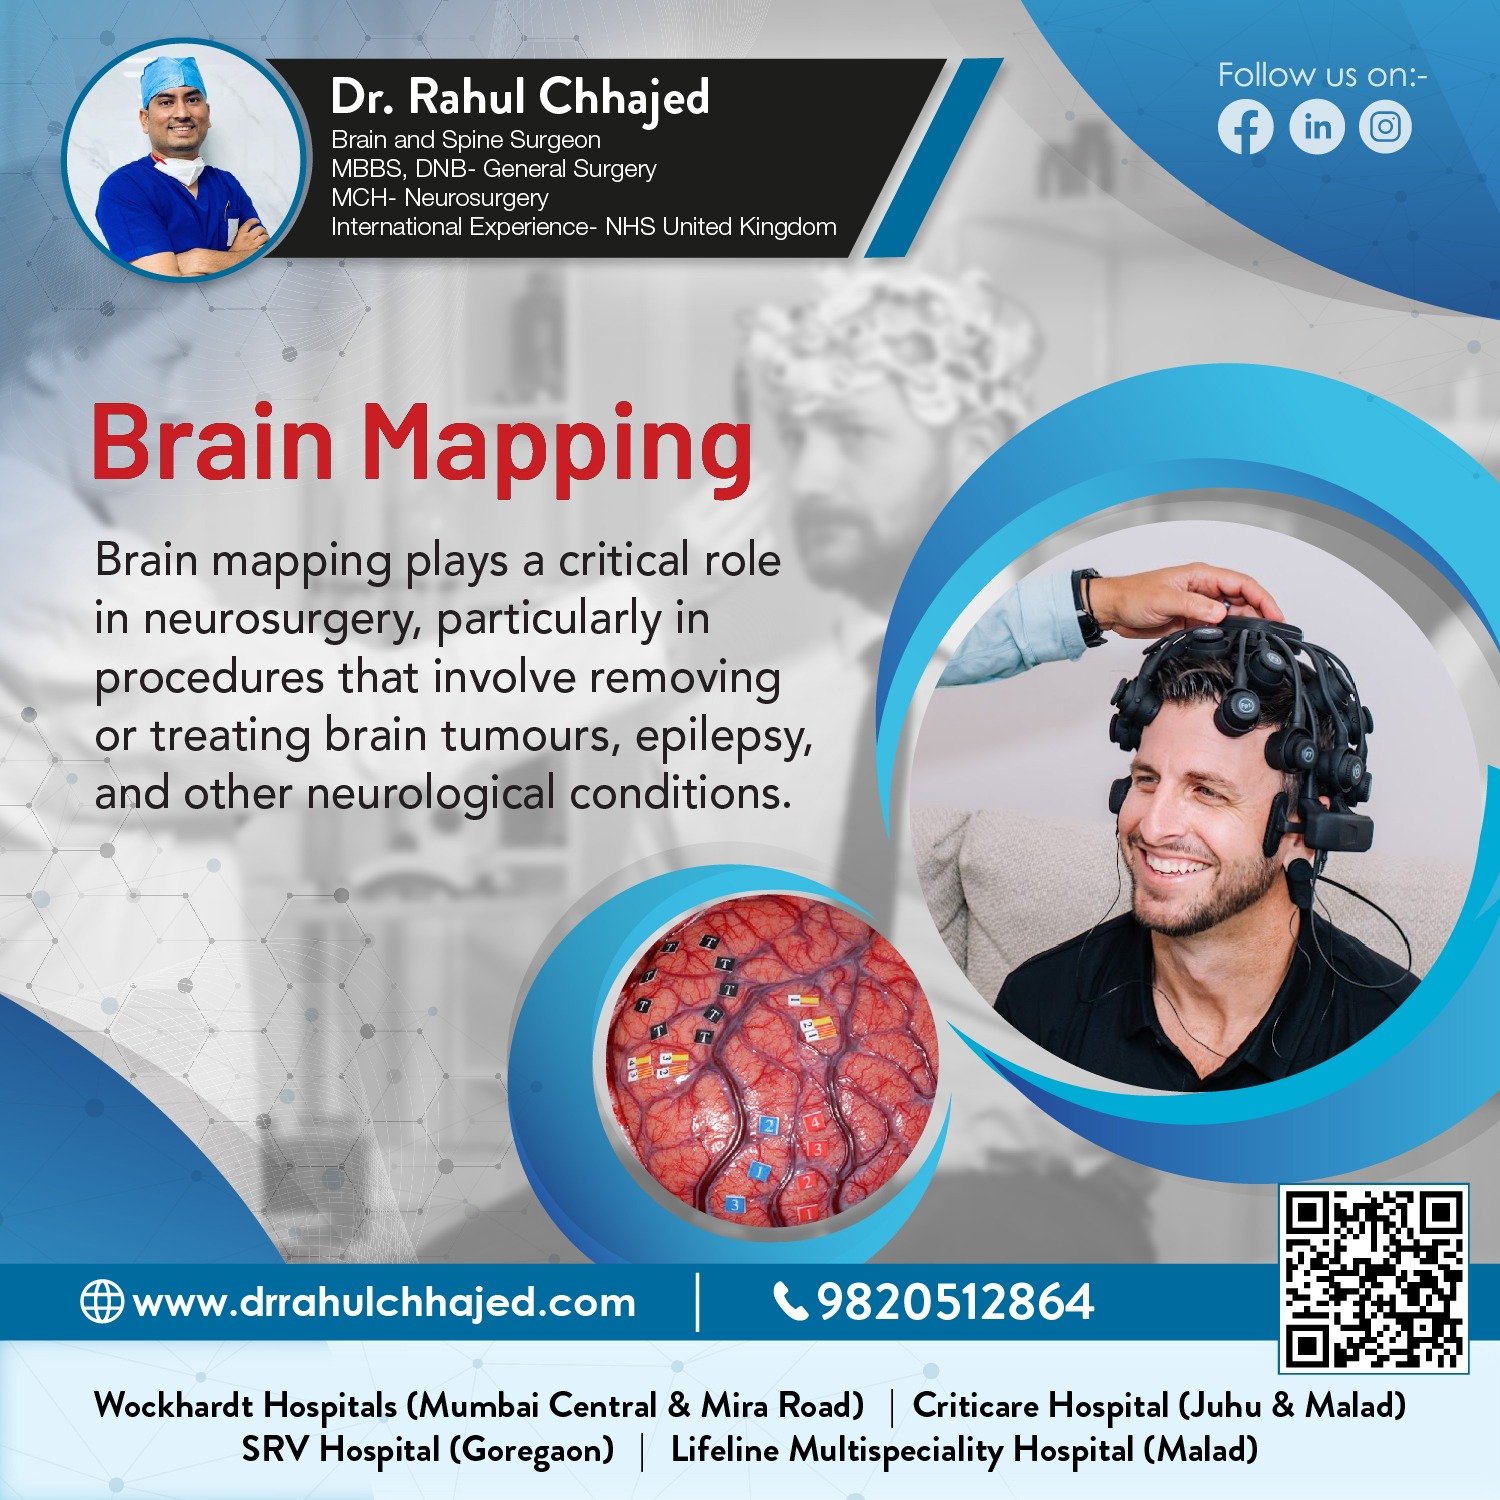

Brain Tumors

Dr. Rahul offers personalized treatment plans for brain tumor patients, taking into account each patient's unique medical history and specific needs. Treatment options may include surgery, radiation therapy, chemotherapy, and targeted therapies.

Epilepsy Surgery

Led by Dr.Rahul our practice offers advanced surgical options for medication-resistant epilepsy. Treatment includes resective surgery, laser therapy, and responsive neurostimulation. We provide personalized care to improve seizure control and quality of life for our patients.